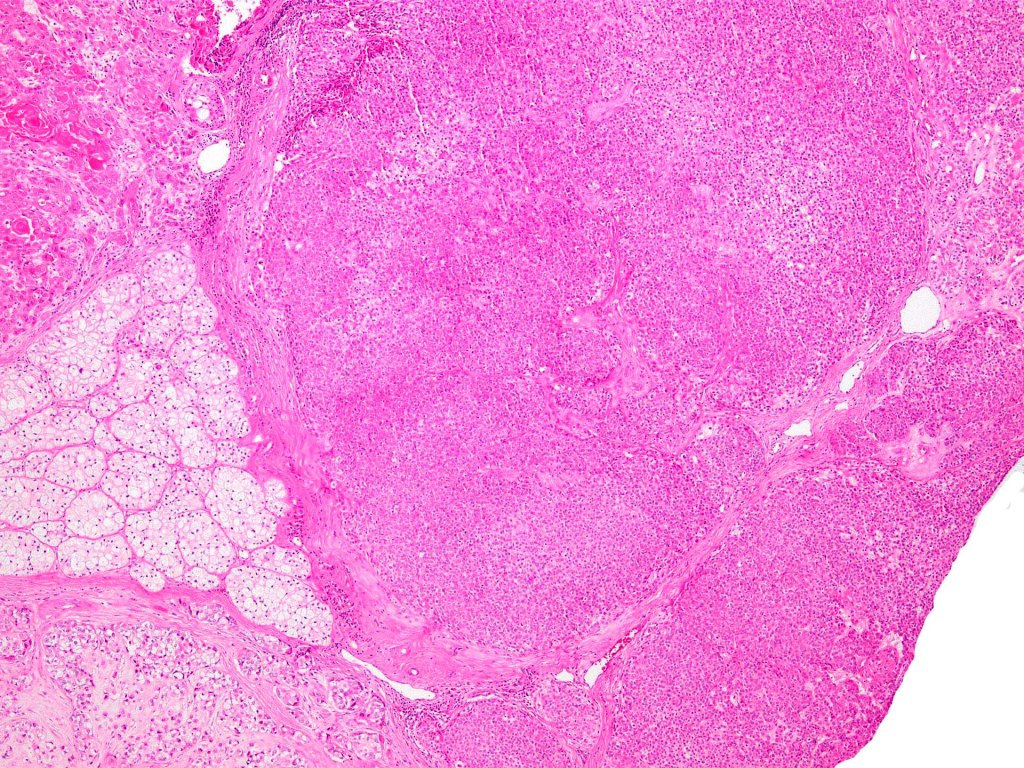

•Biphasic tumor

•Admixture of squamous carcinoma & pleomorphic spindled cell, osteoid, chondroid, MFH-like +/- osteoclast-like giant cells & rarely, smooth muscle, skeletal muscle, myofibroblastic or angiosarcomatous elements